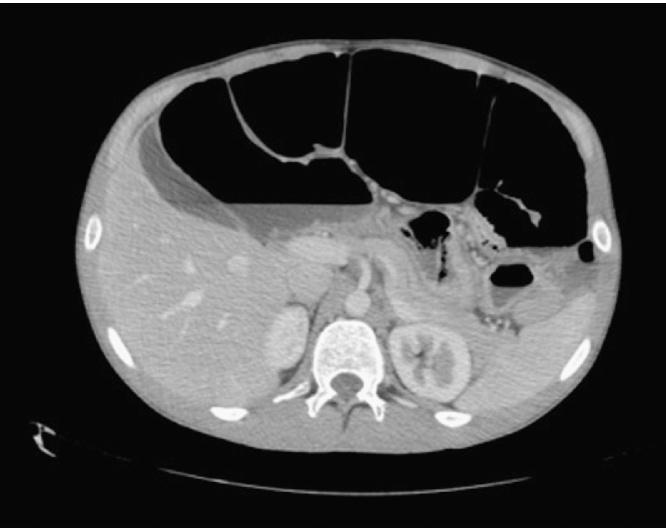

A 20-year old Familial Adenomatous Polyposis (FAP) patient presented with abdominal pain and distention. Abdominal imaging showed small bowel obstruction and hydronephrosis due to a pelvic mass. This mass showed significant enlargement on repeat imaging, and a diagnostic biopsy confirmed desmoid tumour. The mass was deemed unresectable and he was initially started on sulindac and raloxifene. Repeat imaging however showed further enlargement of the tumour, and therefore vinblastine+methotrexate chemotherapy was commenced, with a good response.

一名20岁的家族性腺瘤性息肉病(FAP)患者出现腹痛和腹胀。腹部影像学检查显示因盆腔肿块导致小肠梗阻和肾积水。该肿块在复查影像学检查时显著增大,诊断性活检证实为硬纤维瘤。该肿块被认为无法切除,最初给予舒林酸和雷洛昔芬治疗。然而,复查影像学检查显示肿瘤进一步增大,因此开始使用长春碱+甲氨蝶呤化疗,反应良好。